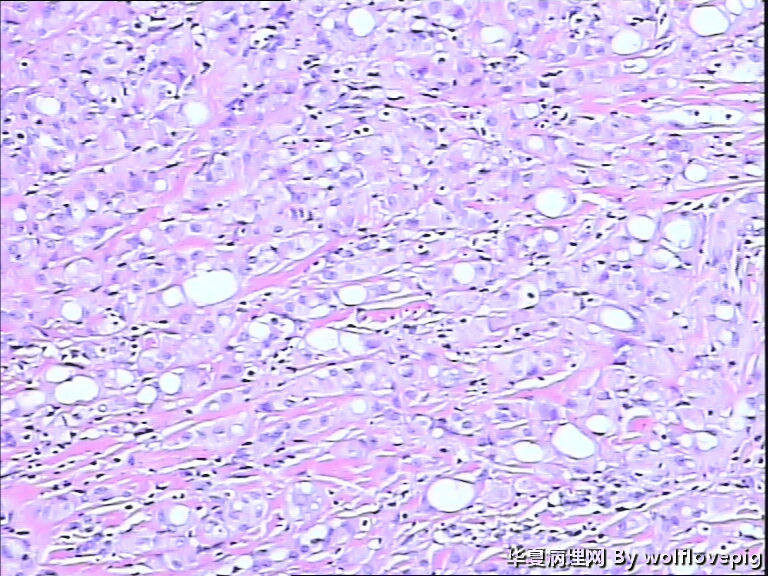

男,60y,左阴囊包块6月,位于附睾尾与睾丸之间,无粘连。灰白结节一个0.7*0.3*0.3,切面灰白、实体 、质韧。

图3

典型的腺瘤样瘤

同意腺瘤样瘤